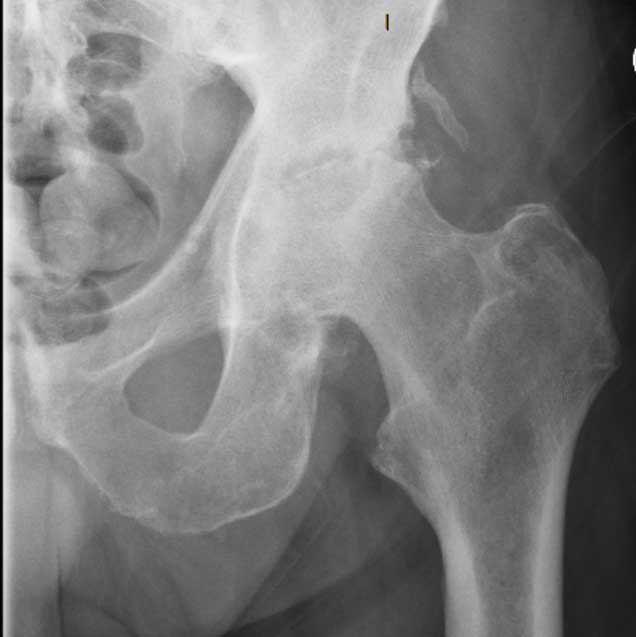

[/vc_column_text][/vc_column][/vc_row][vc_row type=”full_width_background” full_screen_row_position=”middle” column_margin=”default” column_direction=”default” column_direction_tablet=”default” column_direction_phone=”default” bg_color=”#f4f4f4″ scene_position=”center” top_padding=”70″ bottom_padding=”60″ text_color=”dark” text_align=”center” row_border_radius=”none” row_border_radius_applies=”bg” overflow=”visible” overlay_strength=”0.3″ gradient_direction=”left_to_right” shape_divider_position=”bottom” bg_image_animation=”none”][vc_column column_padding=”no-extra-padding” column_padding_tablet=”inherit” column_padding_phone=”inherit” column_padding_position=”all” column_element_direction_desktop=”default” column_element_spacing=”default” centered_text=”true” desktop_text_alignment=”default” tablet_text_alignment=”default” phone_text_alignment=”default” background_color_opacity=”1″ background_hover_color_opacity=”1″ column_backdrop_filter=”none” column_shadow=”none” column_border_radius=”none” column_link_target=”_self” column_position=”default” gradient_direction=”left_to_right” overlay_strength=”0.3″ width=”1/1″ tablet_width_inherit=”default” animation_type=”default” bg_image_animation=”none” border_type=”simple” column_border_width=”none” column_border_style=”solid”][vc_column_text]Arthritis refers to a group of conditions affecting the body’s joints, including the bone, muscle, and surrounding soft tissues. The most common symptoms are joint pain, stiffness, and reduced function, which can lead to disability and reduced quality of life.

Arthritis is a common condition affecting 3.5 million Australians, which is about 15 per cent of the population. Osteoarthritis (OA) and rheumatoid arthritis (RA) are the two most common types. Arthritis has no cure, but its symptoms can be successfully managed with exercise, weight loss, lifestyle changes, and appropriate medication. When symptoms become unmanageable, joint replacement surgery can be considered.